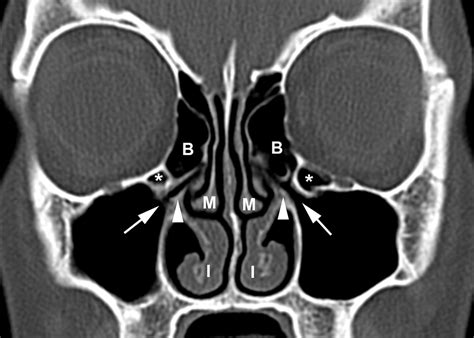

To truly grasp why sphenoid sinus sinusitis is unique, you must first understand the anatomy of the sinuses. We have several sets of paranasal sinuses, which are air-filled cavities in the bones of the skull. The sphenoid sinuses are the most posterior, located directly behind the nose and eyes, nestled at the base of the skull.

• CT Scan: This is the gold standard for diagnosing sphenoid sinusitis. A CT scan of the sinuses provides a detailed, 3D view of the skull, allowing the doctor to see if the sphenoid sinus is opacified (filled with fluid) or if there are structural blockages.